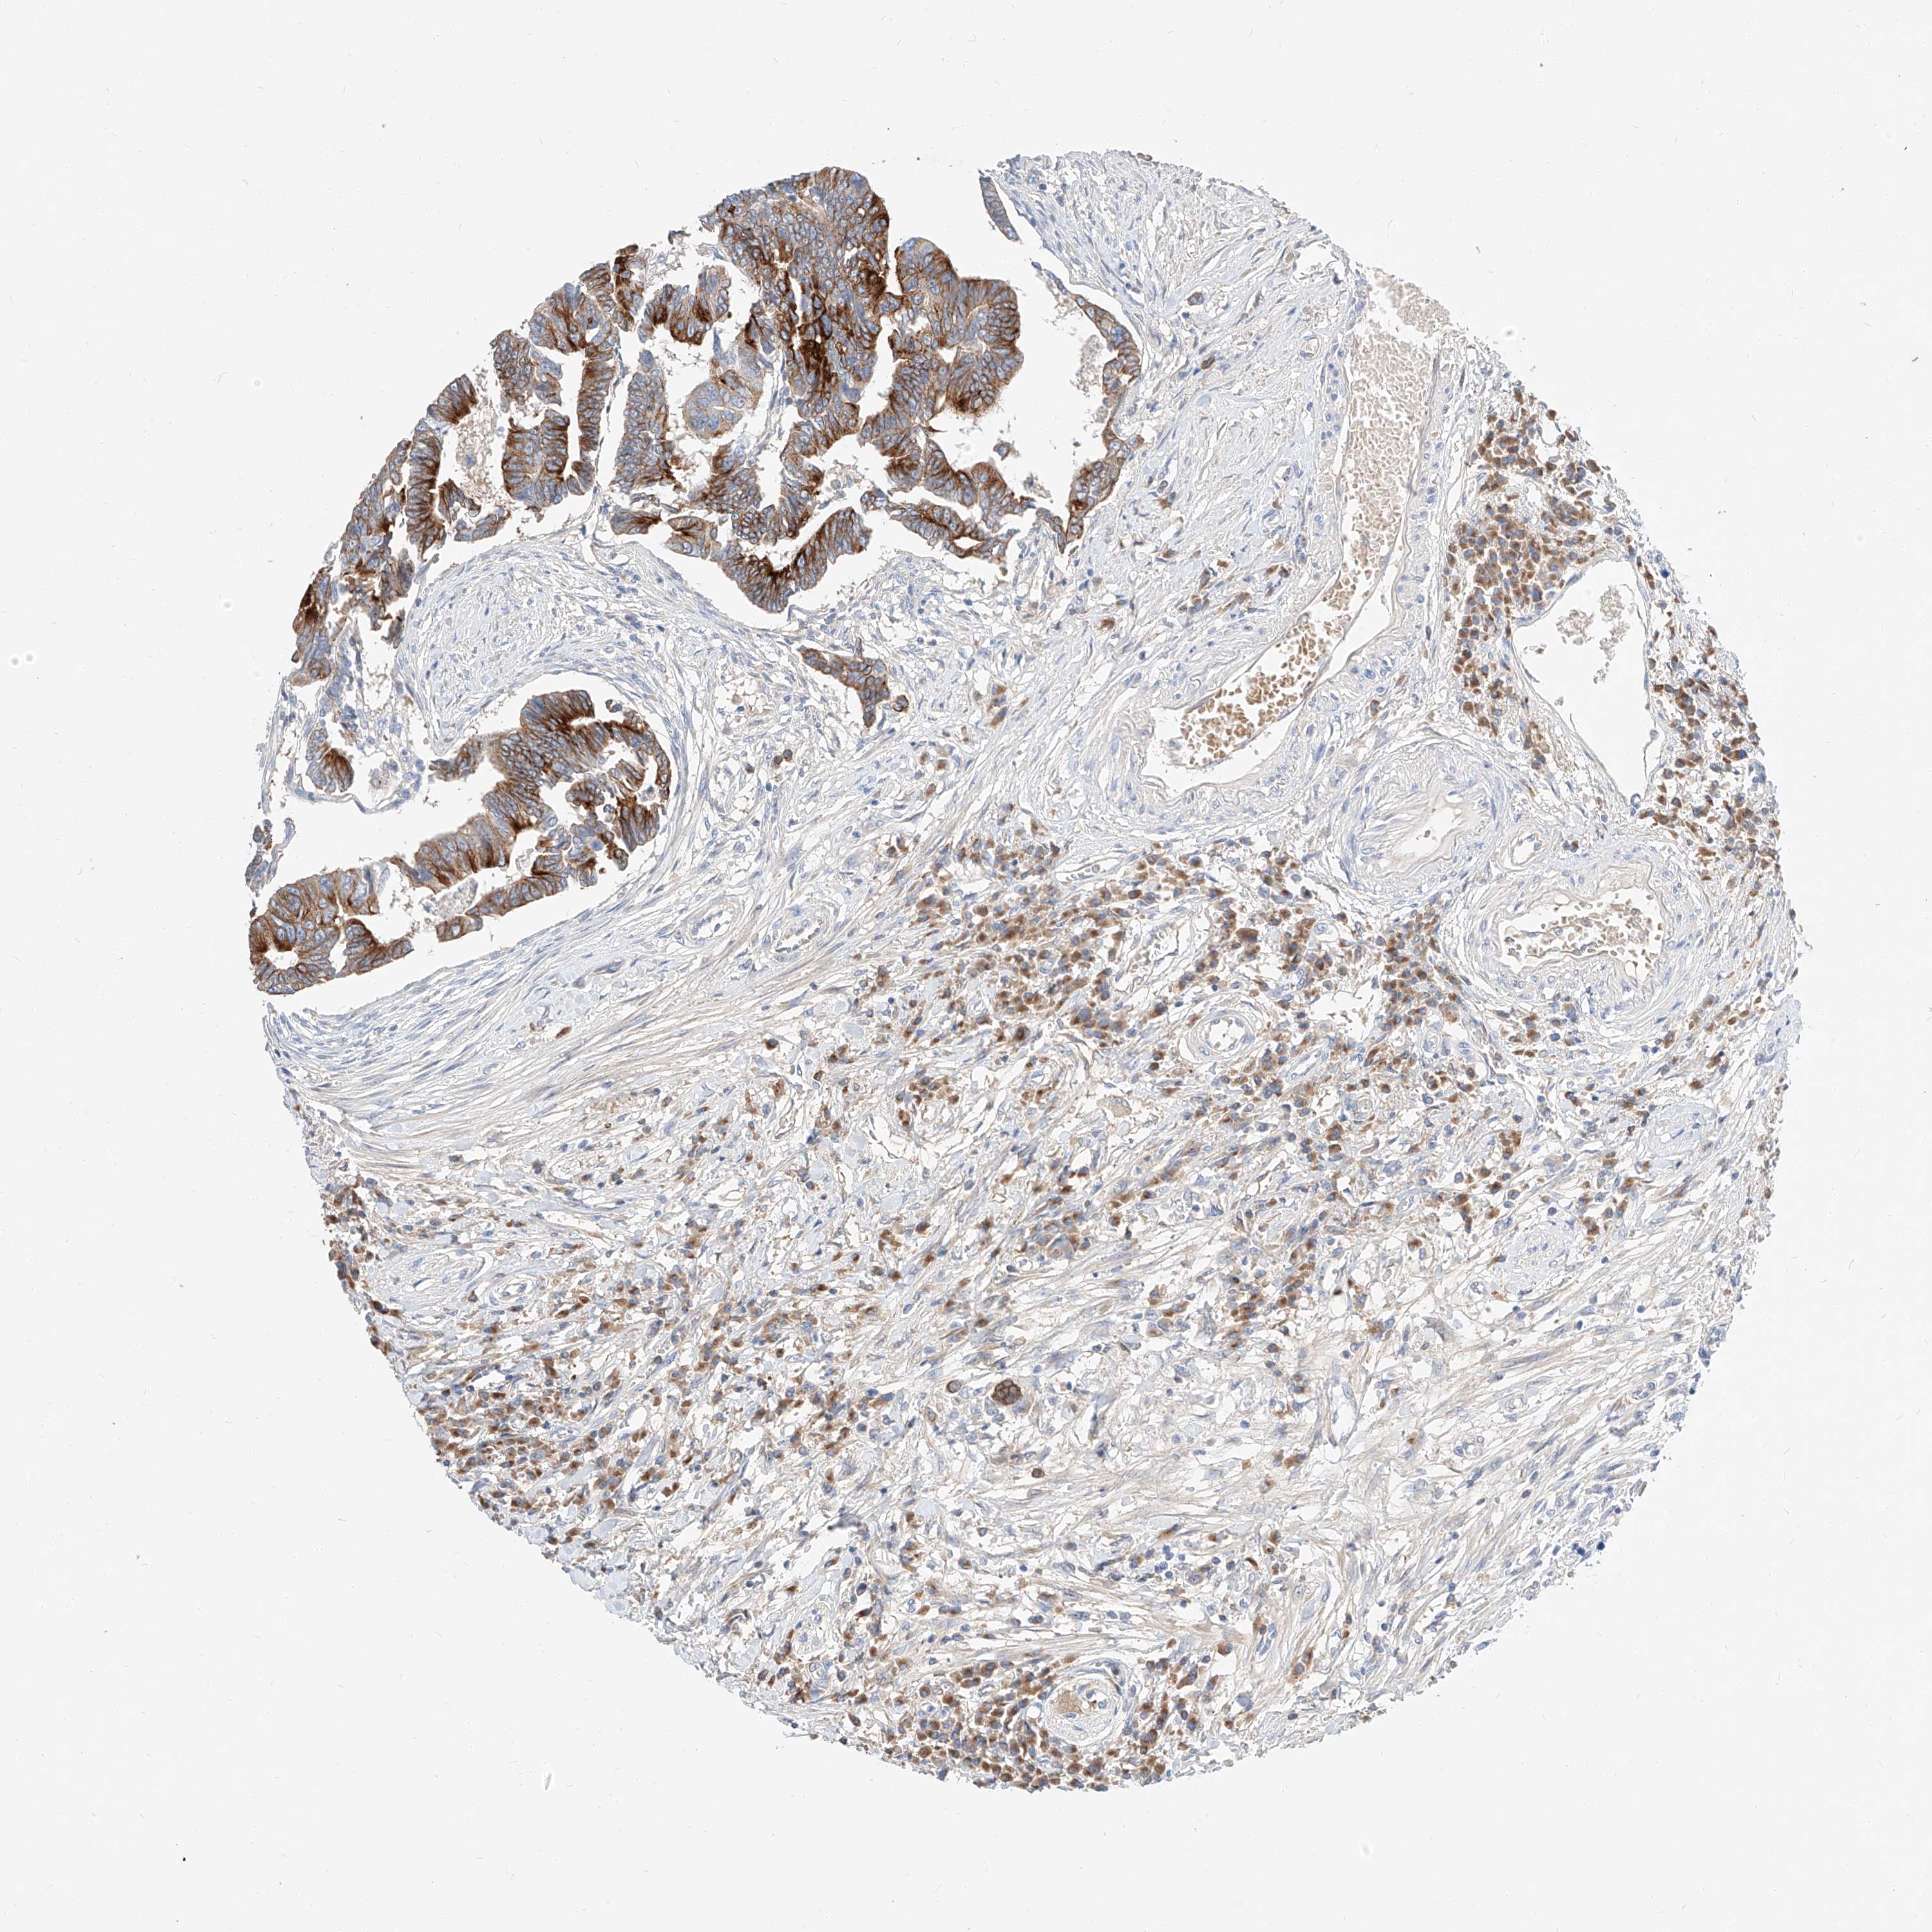

CANCER COLORECTAL CANCER Show tissue menu

ANTIBODIES

AND

VALIDATION